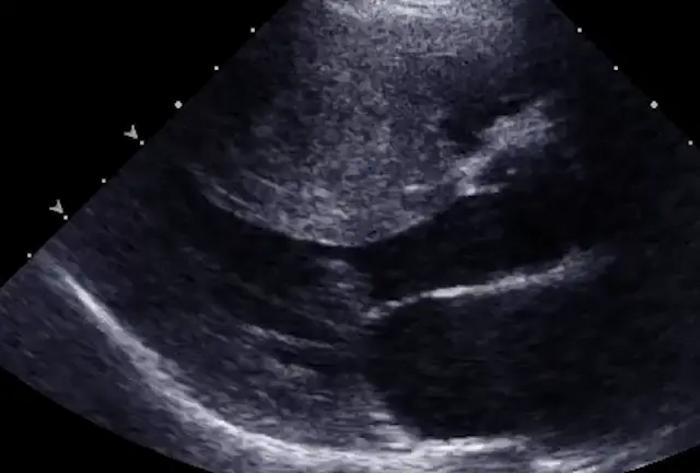

Severe thickening of the heart muscle in a child with hypertrophic cardiomyopathy.

Credit: Dr. Daniel Bernstein, Stanford University

HCM is primarily caused by mutations that thicken heart muscle and, in rare cases, lead to heart failure and cardiac arrest. The new cell line collections will help scientists investigate the impact of specific mutations in myosin, a protein that powers heart contractions, on heart function.